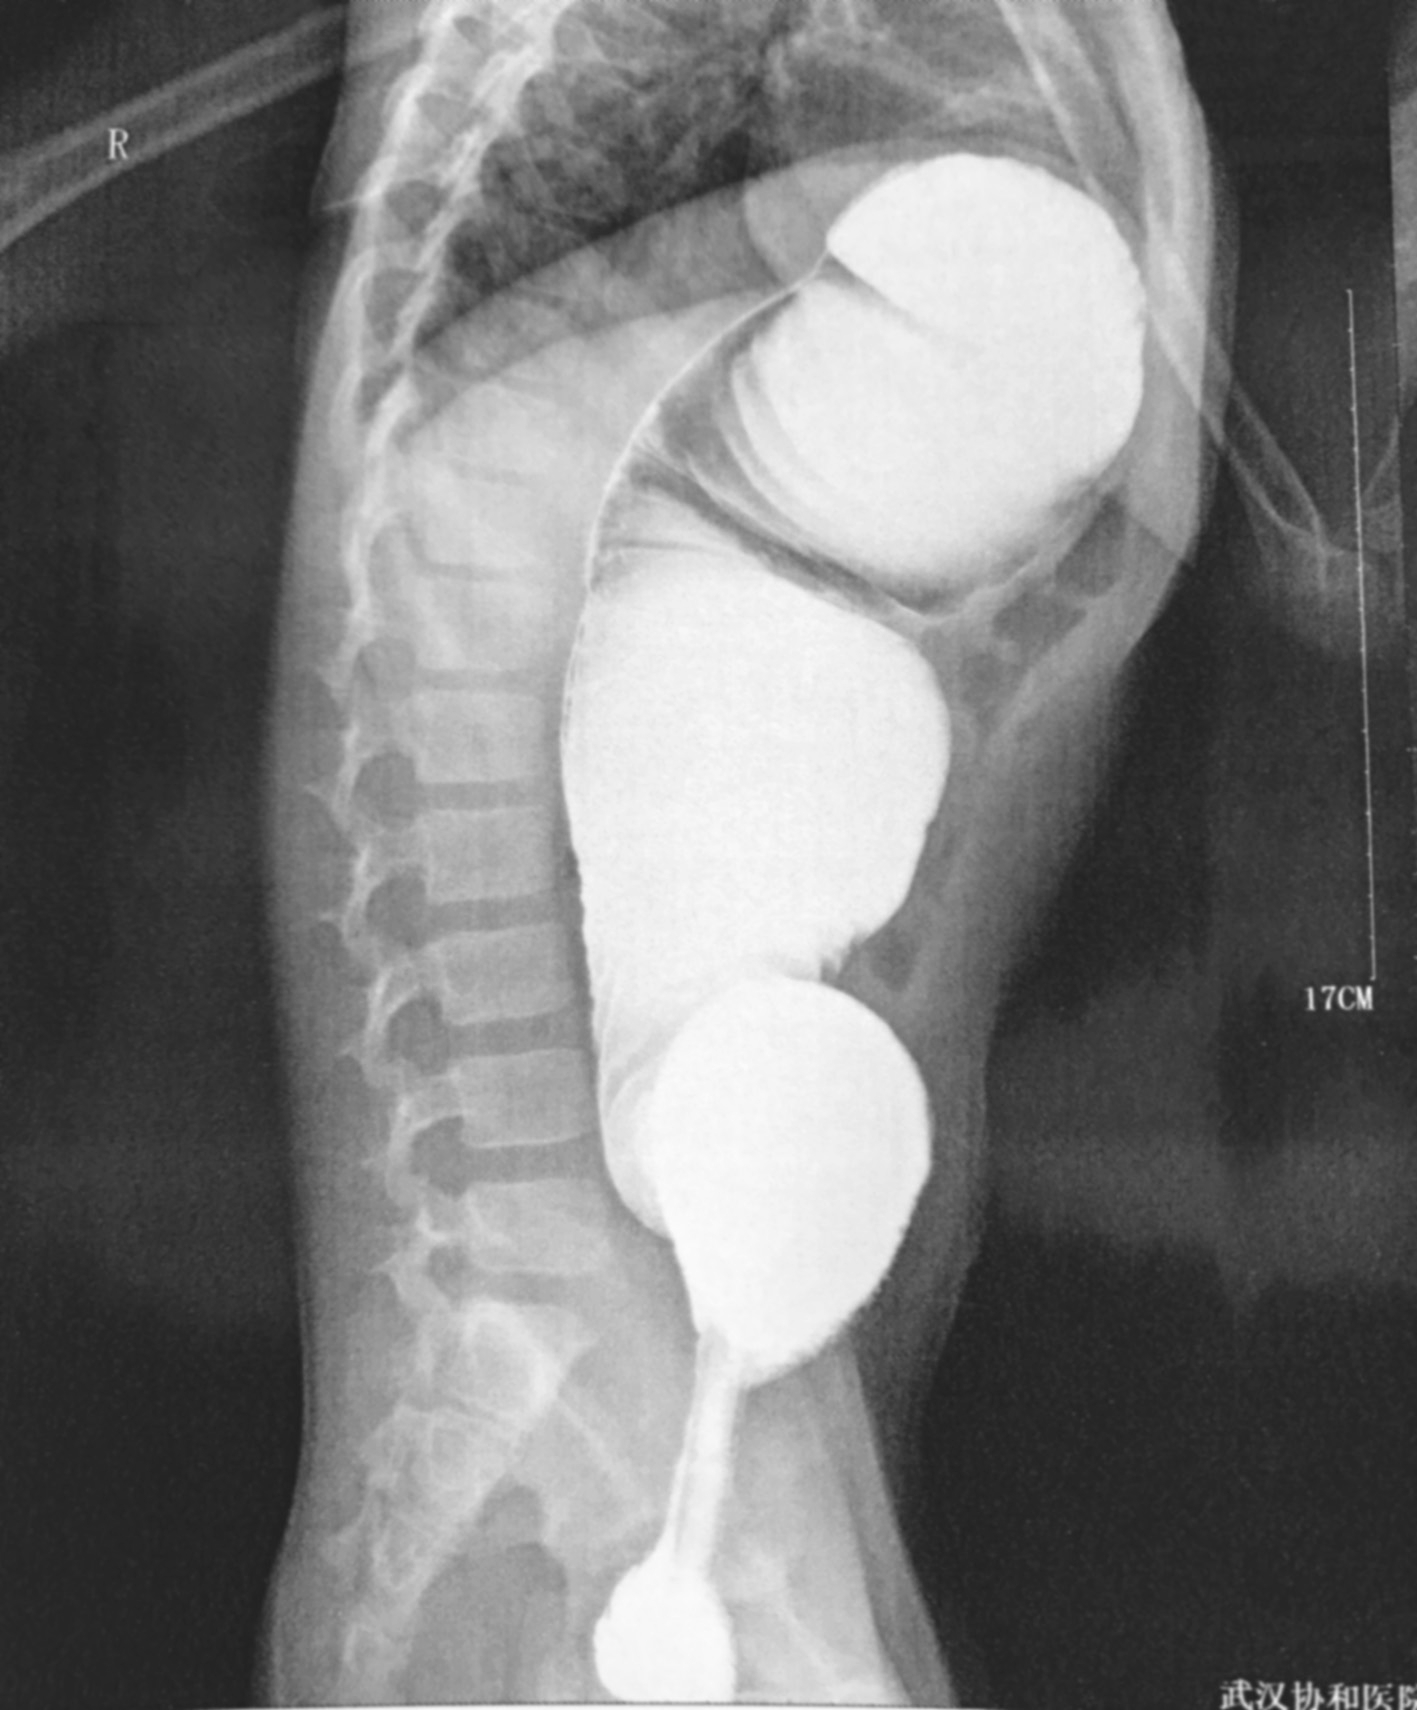

HD患儿立位腹部平片多表现为低位性肠梗阻,腹部可见多发液平、肠管积气、结肠扩张等。这种积气的肠段往往从盆腔开始,顺乙状结肠上行,而其远端则一直未见气体(图3-1)。新生儿时期结肠扩张不如儿童明显,单靠平片诊断比较困难,必须结合病史及其他检查(图3-2)。

图3-1 先天性巨结肠症腹部平片

乙状结肠积气,扩张明显,直肠未见扩张。